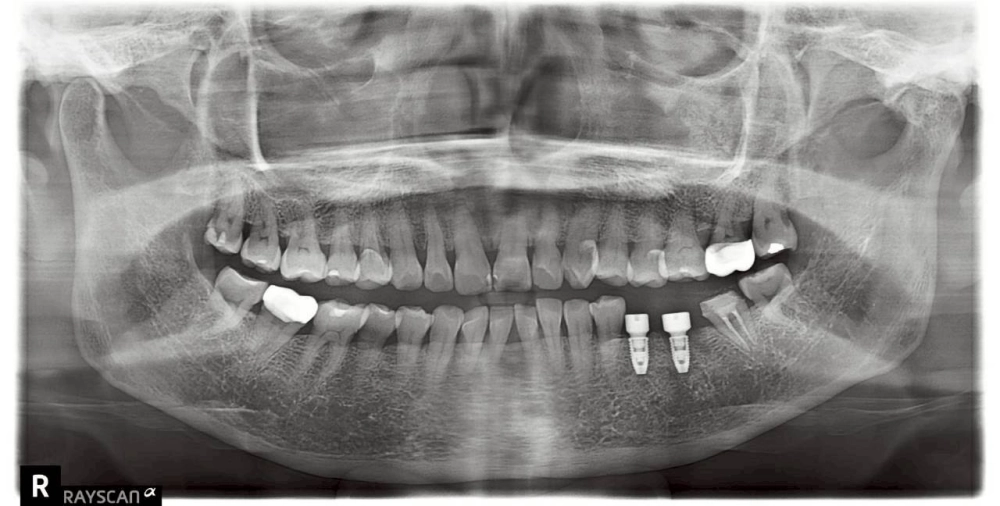

• 植體植入(圖二): 選擇合適直徑與長度的植體,為缺牙區重新打下穩固地基。